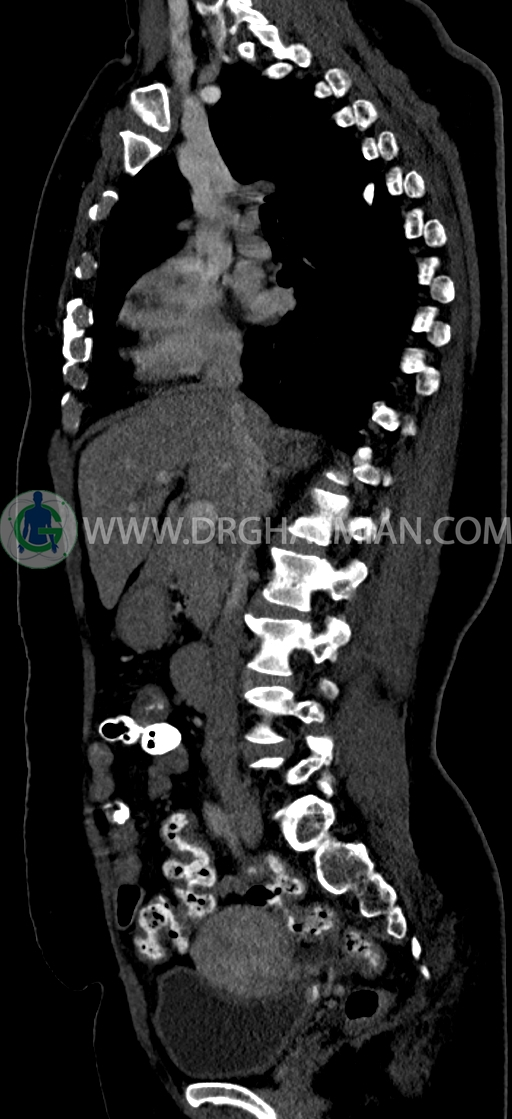

در سي تي اسکن اسپيرال ريه و مدياستن-شکم و لگن با کنتراست خوراکی و وريدی (مولتي ديدکتور 16 با مقاطع ظريف و بازسازي هاي ساژيتال و کرونال) :

–Bridging osteophyte در مهره هاي توراسيک مطرح کننده DISH همراه با کيفوز مشهود است.

–lumbosacral transitional vertebrae

-هرني سوپرا امبليکال با ديفکت به سايز 10mm حاوي چربي و هرني امبليکال با ديفکت به سايز 7mm حاوي چربي مشهود است.